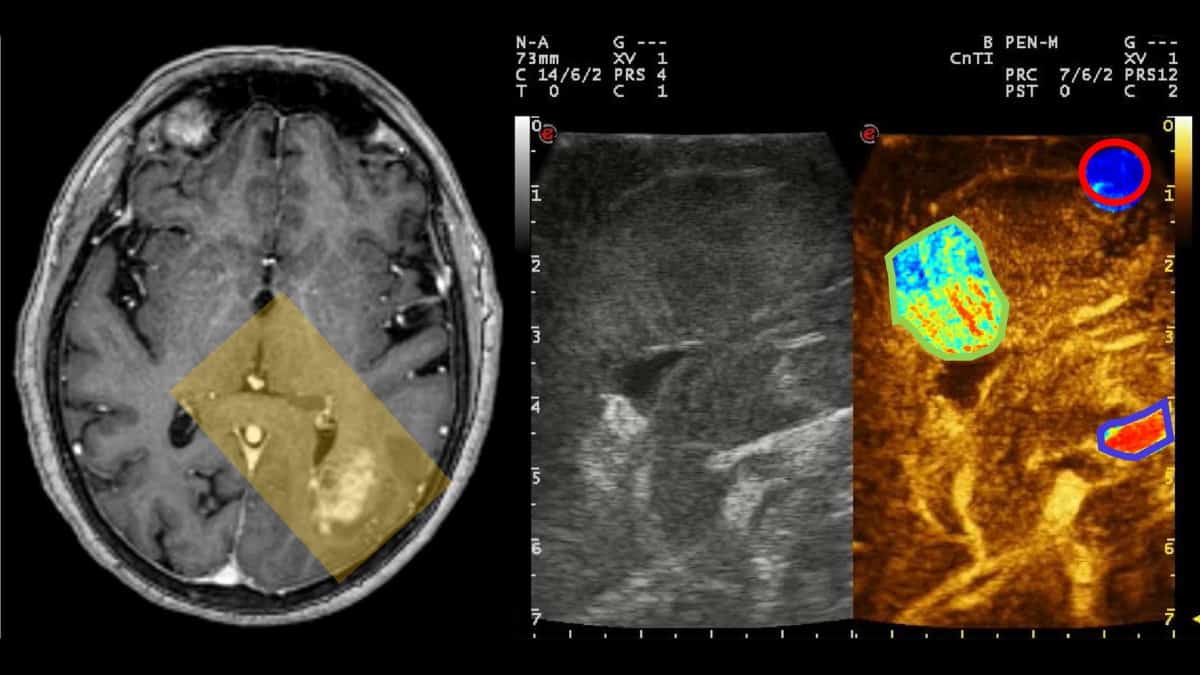

A groundbreaking study has used #FocusedUltrasound and #MicroBubbles to deliver #GeneTherapy safely and efficiently across the blood-brain barrier to help treat Parkinson's Disease (PD). This innovative approach led by Jose Obeso @HMHospital_Int in Madrid, Spain, targeted areas…

Researchers @MedicineUVA have developed a noninvasive method using #focusedultrasound to remove faulty brain circuits that could allow doctors to treat debilitating neurological diseases without the need for conventional brain surgery. eurekalert.org/news-releases/…

Researchers have developed a noninvasive way to remove faulty brain circuits that could allow doctors to treat debilitating neurological diseases without the need for conventional brain surgery.

Understanding cerebral microbubble distribution could open up new avenues for ultrasound-based imaging and therapies physicsworld.com/a/mapping-micr…

A team led by @ChenUltrasound of @WashUengineers is the first to provide direct evidence showing noninvasive, cell-type-specific activation of neurons in the brain by combining ultrasound-induced heating effect and genetics, which they have named sonothermogenetics.

A new device combining focused ultrasound and genetics is showing potential for treating neurological conditions, such as Parkinson's and epilepsy.

Scientists developed a brain stimulation technique using focused ultrasound that is able to turn specific types of neurons in the brain on & off & precisely control motor activity without surgical device implantation sciencedaily.com/releases/2021/…